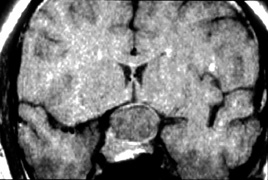

Optic nerve hypoplasia, unless subtle, usually is diagnosed on fundus examination. Although most cases are idiopathic, maternal gestational diabetes and use of phenytoin are well-known risk factors; more recent epidemiologic studies have also suggested that young maternal age, first parity, smoking, and use of fertility and antidepressant drugs may also play a role.27 If bilateral, this condition may be associated with congenital nystagmus. De Morsier's syndrome (septo-optic dysplasia) refers to the constellation of bilateral optic nerve hypoplasia, absence of the septum pellucidum (Fig. 5), thinning or absence of the corpus callosum, dysplasia of the anterior third ventricle, and pituitary dysfunction (see Chapter 5, Fig. 9). Brodsky and Glasier28 broadened the spectrum of this condition. In a study of 40 children, some optic nerve anomalies were isolated, but in other children, midline craniofacial defects, hemispheric gray matter dystrophic anomalies, and posterior pituitary ectopia were noted. Of 21 cases of optic nerve hypoplasia described by Zeki et al,29 there were midline central nervous system defects in six and endocrine deficiencies in nine. In the series of 35 patients with bilateral optic nerve hypoplasia described by Siatkowski et alet al30 neuroradiographic abnormalities were seen in 46% and endocrinopathies in 27%. Growth hormone deficiency was the most common endocrine abnormality. The visual spectrum ranged from 20/20 in one case to no light perception in 34% of patients; 80% were legally blind (20/200 or less in both eyes). Absence of the septum pellucidum and corpus callosum, with panhypopituitarism, occurred in only 11.5% of all patients with bilateral optic nerve hypoplasia. Recently, a sporadic mutation in the HESX1 gene has been reported to cause optic nerve hypoplasia with pituitary insufficiency.31

Fig. 5. Magnetic resonance image of patient with bilateral optic nerve hypoplasia demonstrating absence of septum pellucidum with single midline ventricle.